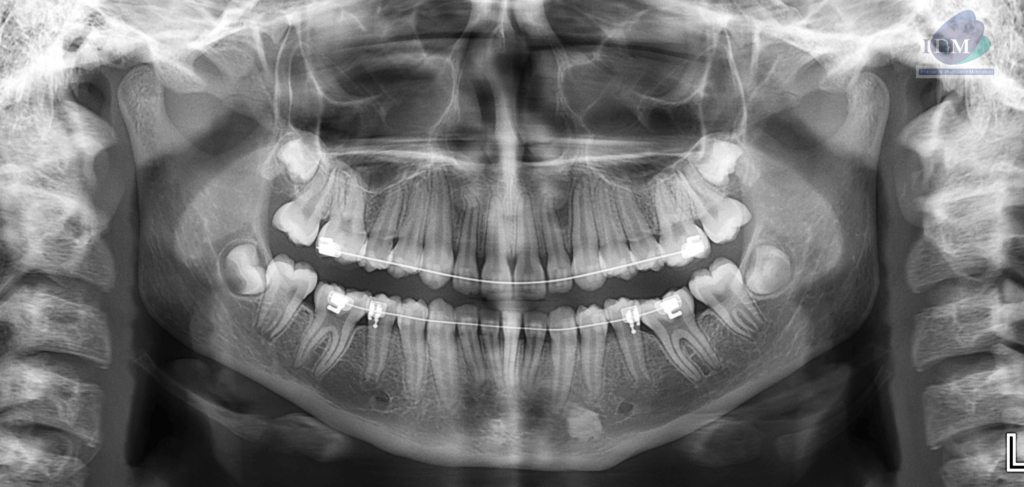

A la evaluación de la tomografía volumétrica (CBCT) en los cortes axiales (Figura 2) y transaxiales (Figura 3), se aprecia imagen hiperdensa intraosea, de limites definidos y forma irregular, que se extiende entre tabla ósea vestibular y lingual, sentido cefálico caudal desde nivel apical de pieza 33 hasta cortical superior del conducto dentario inferior, comprometiendo la cortical superior del conducto dentario inferior.

CORTES TRANSAXIALES